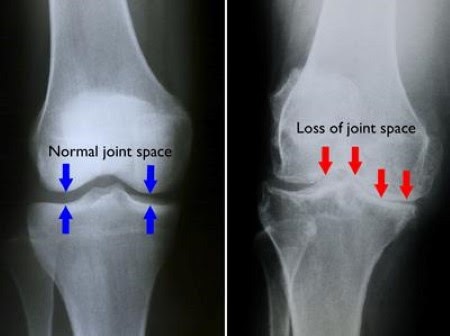

**영상검사

단순 방사선 사진이 가장 유용합니다. 초기에는 정상 소견을 보일 수 있으나 점진적으로 관절 간격의 감소가 나타나며 연골 아래 뼈의 음영이 짙어지는 경화 소견을 볼 수 있습니다. 더욱 진행되면 관절면의 가장 자리에 뼈가 웃자란 듯한 골극이 형성되고 관절면이 불규칙해집니다. 이차성 관절염의 경우 원인이 되는 과거 외상이나 질환의 흔적 혹은 변형 등이 관찰되기도 합니다. 다만 방사선학적 변화가 증상 및 활동력의 심한 정도를 그대로 반영하는 것은 아니어서 40세 이상에서 90% 정도는 방사선학적으로 퇴행성 변화를 보이지만 이 중 30% 정도만이 증상을 보이게 됩니다.

Plain radiograph

grade 0: normal

grade 1: possible joint space narrowing and subtle osteophytes

grade 2: definite joint space narrowing, defined osteophytes and some sclerosis, especially in the acetabular region

grade 3: marked joint space narrowing, small osteophytes, some sclerosis and cyst formation and deformity of femoral head and acetabulum

grade 4: gross loss of joint space with above features plus large osteophytes and increased deformity of the femoral head and acetabulum